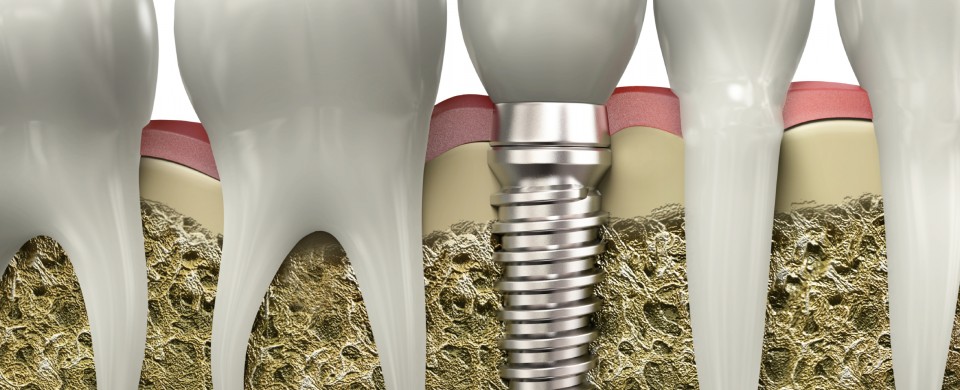

İmplant tedavisini bu yapay kökleri uygularken sabit ve hakaretli protezler yapmak üzere iki şekilde değerlendiriyoruz. Sabit protezlerde ne yapıyoruz? Tek diş eksikliği olabilir birden fazla diş eksikliği olabilir, burada köprü ayağı olarak kullanabiliyoruz. Bir de hakaretli protezlerde yani takıp çıkarmalı protezler diye tabir edilen protezlerde kullanıyoruz. Özetle; diş eksikliğinde tek diş ayağı olarak ya da köprü ayağı olarak implant tedavisinde kullanabiliyoruz. Hakaretli protezlerde de özellikle alt çenede protez stabilizasyonunda problemler çok fazla yaşanmakta. Çünkü çene kemiği fonksiyonsuz kaldığı zaman eriyor ve eriye bu çene kemiğine biz implant koyarak daha sonra yapılacak protezi rahatlıkla kullanılması için bazı parçalar yerleştiriyoruz. Tıpkı topuz gibi düşünülebilen bu parçaların üstüne protez yapıldığı zaman protezin o mevcut dişsiz halinde haraketli protezin oynama gibi sıkıntılarını ortadan kaldırmış oluyoruz. Dolayısı ile sadece sabit dişlerde değil sabit protezlerde değil hakaretli protezleride ortadan kaldırmak yada mevcut haraketli protezin kullanışlılığını daha rahat yeme içme işlemlerini yapma adına implant tedavisi sıklıkla kullanılmaktadır.

Hangi Durumlar da İmplant Tedavisi Uygulanabilir?

implant